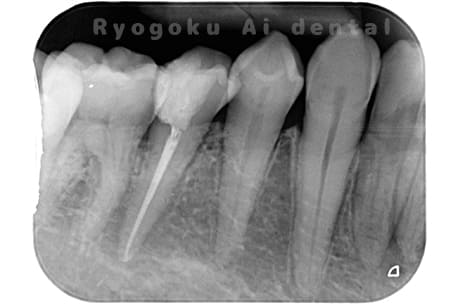

Case02

- 原因

- 慢性根尖性歯周炎

- 治療期間

- 3ヶ月

- 治療内容

- マイクロエンド

- 治療費用

- 121,000円

噛むと痛みが出る、とのことで来院した患者様です。他院での根管治療を終えてましたが、根尖病変を認めるため、マイクロエンドを行いました。